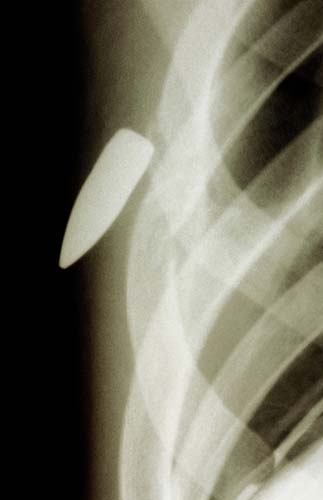

Göğüse saplanmış bir kurşun